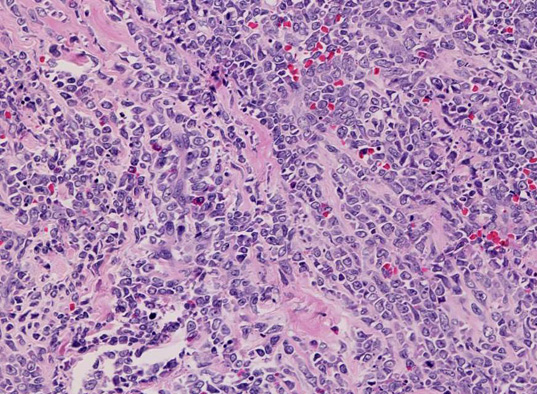

拡大像では, 類円形, 卵円形, non-cleaved nucleiをもつN/C比大の大きさのそろった細胞がシート状密に浸潤増殖している.

クロマチンは繊細で核は淡明, 核小体を1から数個もつ.